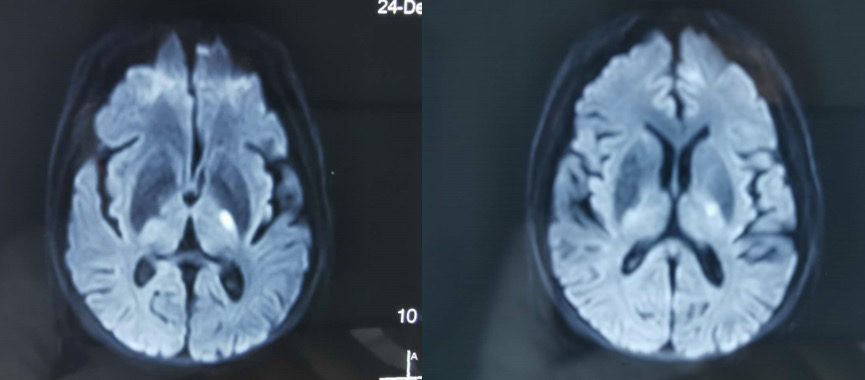

图1头颅核磁(2019-12-24)

患者2019-12-14突发右侧肢体活动不利,表现为右手持物困难,右下肢尚可行走,伴有吞咽困难、饮水呛咳,就诊于我院行头颅核磁检查提示左侧内囊后肢急性脑梗死,于我院住院治疗后病情好转,住院期间完善头颅核磁提示双侧颈内动脉动脉瘤可能,进一步完善CTA提示双侧颈内动脉眼动脉段动脉瘤,患者为进一步治疗以“颅内动脉瘤”入院。